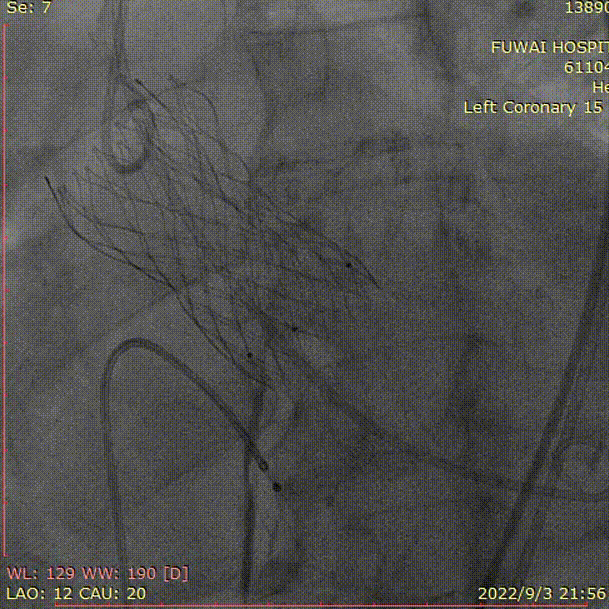

六、急诊TAVR操作过程

4、植入VenusA-Plus  L29,术后造影冠脉显影良好

初始释放位置定位

完全释放

5、25mm球囊后扩(右窦钙化重,由于钙化挤压,瓣架展开不良)

球囊后扩张